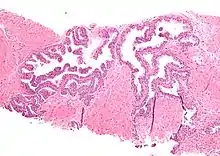

| Micrograph showing high-grade prostatic intraepithelial neoplasia. H&E stain. | |

Microscopically, PIN is a collection of irregular, atypical epithelial cells. The architecture of the glands and ducts remains normal. The epithelial cells proliferate and crowding results in a pseudo-multilayer appearance. They remain fully contained within a prostate acinus (the berry-shaped termination of a gland, where the secretion is produced) or duct. The latter can be demonstrated with special staining techniques (immunohistochemistry for cytokeratins) to identify the basal cells forming the supporting layer of the acinus. In prostate cancer, the abnormal cells spread beyond the boundaries of the acinus and form clusters without basal cells. In HGPIN, the basal cell layer is disrupted but present. PIN is primarily found in the peripheral zone of the prostate (75-80%), rarely in the transition zone (10-15%) and very rarely in the central zone (5%), a distribution that parallels the zonal distribution for prostate carcinoma.[6]

Several architectural variants of PIN have been described, and many cases have multiple patterns. The main ones are tufting, micropapillary, cribriform, and flat. Although these different appearances may cause confusion with other conditions, they have not been found to be of clinical importance. Rarer types are signet-ring-cell, small-cell-neuroendocrine, mucinous, foamy, inverted, and with squamous differentiation.[3]